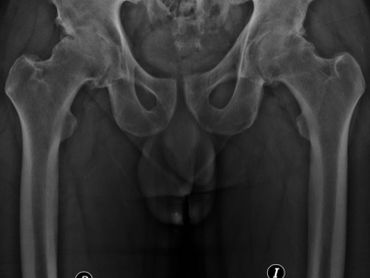

Reemplazo articular de ambas caderas en un tiempo